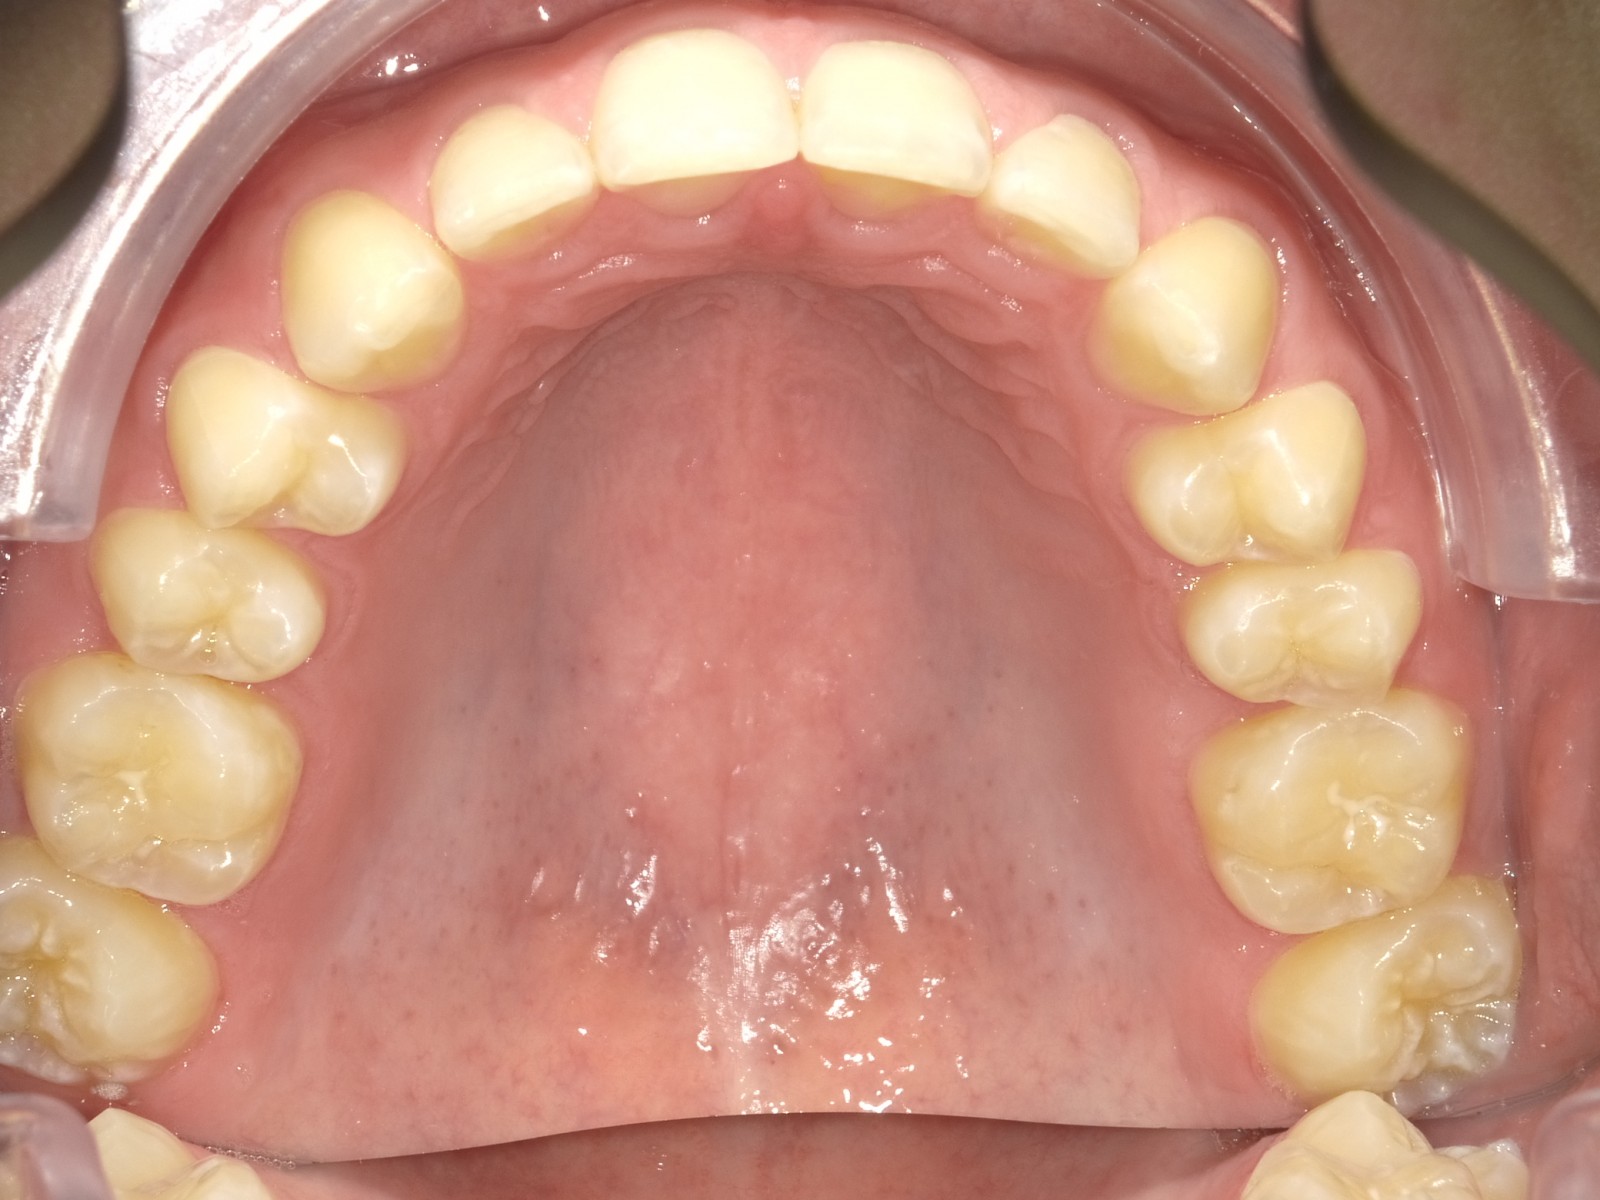

1-26 maand Volledig vast onderkaak + Transforce onderkaak